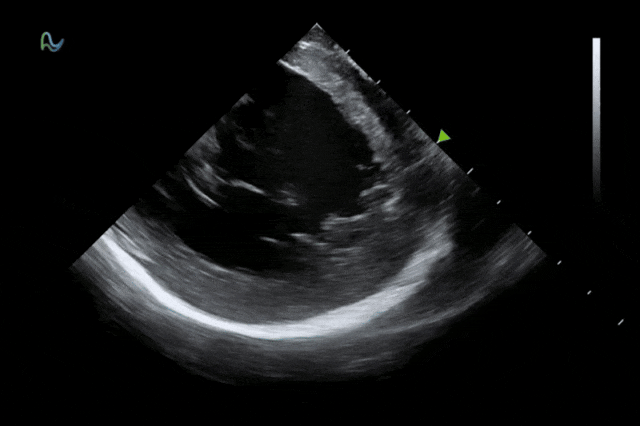

本次获批的ICE导管在全球首次采用了80阵元大孔径高密度探头设计,较传统普通的64阵元产品大幅度提升了成像分辨率、成像深度和图像对比度,可清晰辨识心脏细微结构和血流,为复杂手术给予更可靠的超声成像支持。同时,8F导管凭借更小的外径,显著提升导管顺利获得性和操控性,对病人创伤更小,尤其适合血管条件受限或小心脏患者;10F导管则凭借其优质的成像质量,为复杂心脏介入手术给予精准的影像引导。